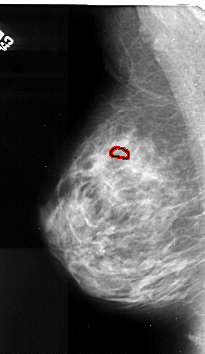

A_1105_1.LEFT_MLO

LEFT_MLO LINES 5296 PIXELS_PER_LINE 3061 BITS_PER_PIXEL 16 RESOLUTION 42 OVERLAY

FILE: A_1105_1.LEFT_MLO.OVERLAY

TOTAL_ABNORMALITIES 1

ABNORMALITY 1

LESION_TYPE CALCIFICATION TYPE PLEOMORPHIC DISTRIBUTION CLUSTERED

ASSESSMENT 4

SUBTLETY 2

PATHOLOGY MALIGNANT

TOTAL_OUTLINES 1

BOUNDARY